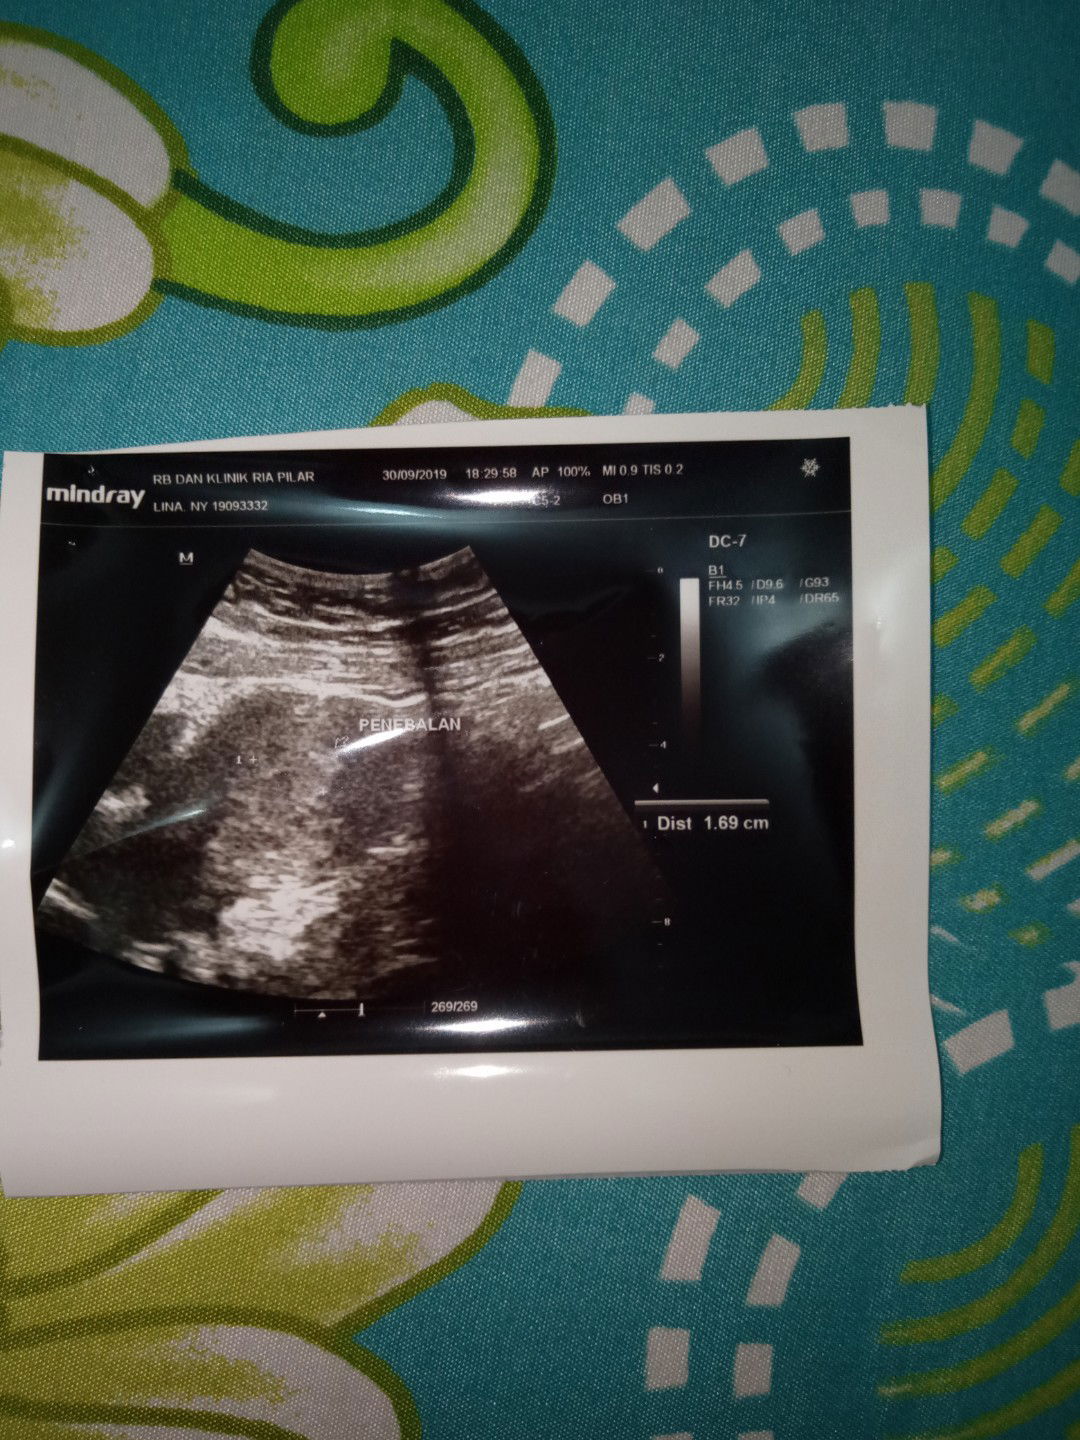

USG

Bu kemarin sempet pas tgl 28 agustus akhir saya tespek dan hasilnya garis 2 Trus tgl 30 agustus saya pastikan ke dokter kandungan buat di usg dan hasilnya belum kelihatan bun Saya bngung karna dokternya nerangin kandungan ku gak begitu jelas tapi kada dokter belum kelihatan 2minggu lagi disuruh cek kesitu lagi Cuma dikasih hasil usg seperti itu Masih galo sebenarnya hamil apa gak si bun ada yg tau hasil usg itu usia kandungan berapa minggu ? Soalnya saya gak ada rasa mual sama pusing bun